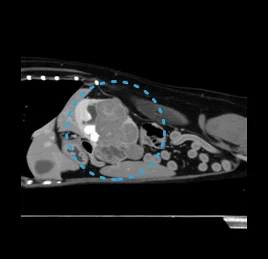

• 혈관 질환

간문맥전신단락 (PSS), 혈전색전증, 동맥관개존 (PDA),

우대동맥궁잔존 (PRAA)

• 혈관 이상 - PSS